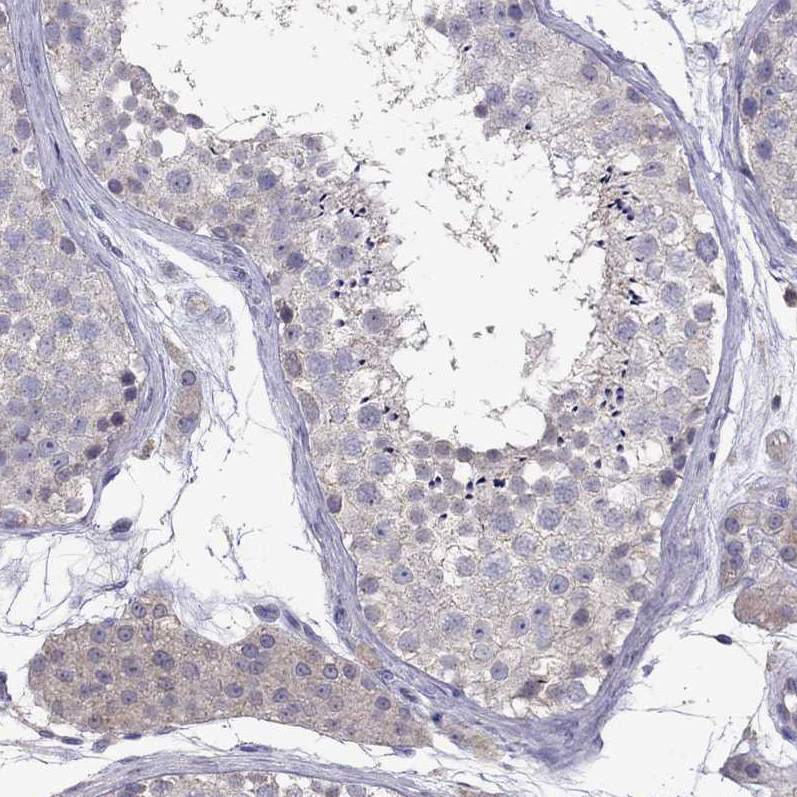

Immunohistochemistry analysis in human cerebral cortex and skeletal muscle tissues using HPA050902 antibody. Corresponding RTP5 RNA-seq data are presented for the same tissues.